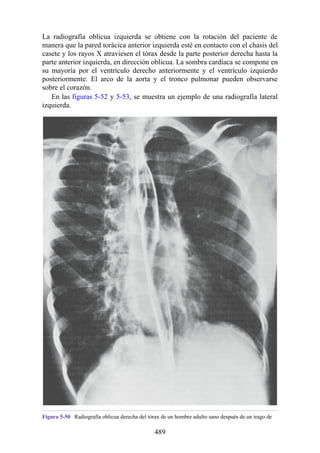

anterior continua (véase fig. 2-4A). A medida que el desarrollo continúa, se

desarrolla el ángulo lumbosacro en la unión de las vértebras L5 y S1, para así

formar dos curvaturas cóncavas anteriormente. Después del nacimiento, la